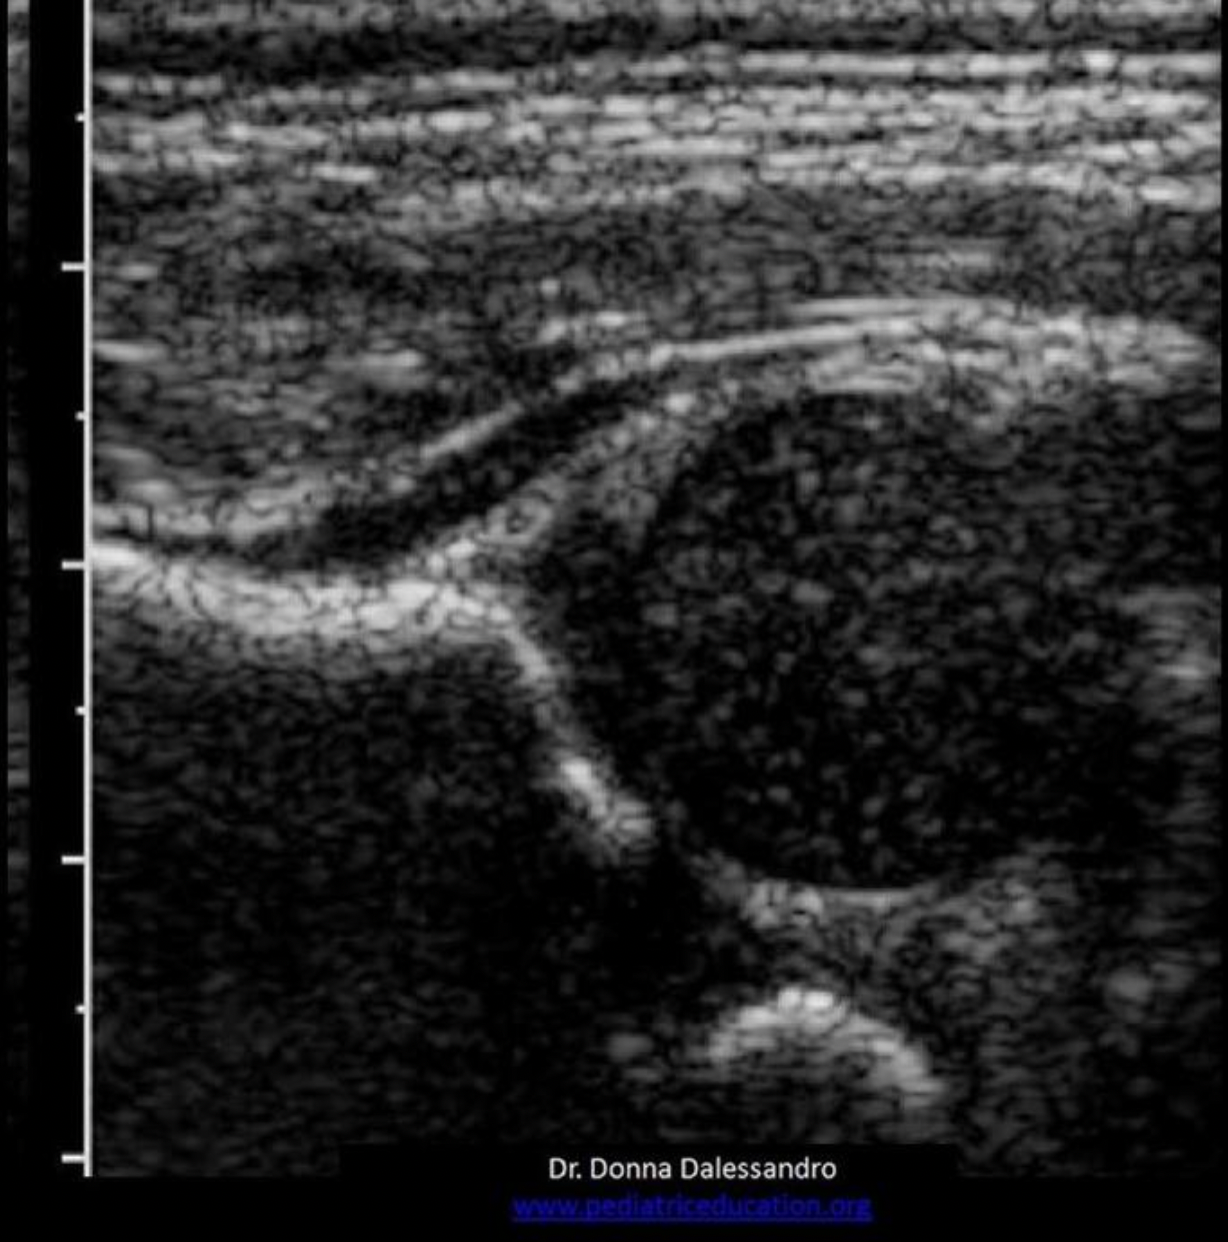

Which of the following is a characteristic of a normal lymph node?

C. thin hypochoic rim with hyperechoic central hilum

Normal lymph nodes are ovoid in shape. They do not demonstrate posterior enhancement. As lymph nodes enlarge with abnormal fluid accumulation, they appear more rounded and hypochoic/anechoic. The "plump" cortex causes decreased visualization of the central hilum. Color Doppler can be used to locate the hilum and main vascular supply. Posterior enhancement is present in structures posterior to abnormal nodes with significant fluid accumulation.

While scanning the thyroid, you identify a 0.6cm ovoid structure outside the thyroid, lateral to the left carotid artery. The structure has a thin hypoechoic rim surrounding a hyperechoic center. These findings are most suggestive of:

D. normal lymph node

Normal lymph nodes are ovoid in shape. They do not demonstrate posterior enhancement. As lymph nodes enlarge with abnormal fluid accumulation, they appear more rounded and hypoechoic/anechoic. The "plump" cortex causes decreased visualization of the central hilum. Color Doppler can be used to locate the hilum and main vascular supply. Posterior enhancement is present in structures posterior to abnormal nodes with significant fluid accumulation.

Find the normal lymph node

A normal lymph node is oval in shape and demonstrates a thin hypoechoic rim of tissue around an echogenic hilum. Abnormal lymph nodes demonstrate a more rounded shape, thickened cortex that can appear anechoic. and there is loss of differentiation of the hilum.